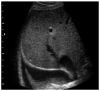

Point-of-care thoracic ultrasound at the patient's bedside has increased significantly recently, especially in pediatric settings. Its low cost, rapidity, simplicity, and repeatability make it a practical examination to guide diagnosis and treatment choices, especially in pediatric emergency departments. The fields of application of this innovative imaging method are many and include primarily the study of lungs but also that of the heart, diaphragm, and vessels. This manuscript aims to describe the most important evidence for using thoracic ultrasound in the pediatric emergency setting.